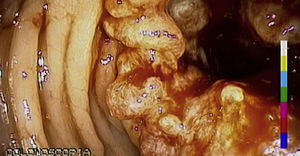

El signo de Leser-Trélat se caracteriza por la aparición súbita y el rápido crecimiento en número y tamaño de múltiples queratosis seborreicas, relacionado con una neoplasia subyacente. Masculino de 57 años de edad, con 4 meses de evolución con cambios en hábitos defecatorios, refiriendo adelgazamiento de las evacuaciones, así como la presencia de rectorragia ocasional con manchado lineal de las evacuaciones, asociado a esto refiere la aparición de hace un año de lesiones dérmicas en su espalda que aparecieron súbitamente y se incrementaron en número. En la colonoscopia con lesión circunferencial a 13cm del margen anal (fig. 1) con reporte histopatológico de adenocarcinoma. En la espalda del paciente (fig. 2), se aprecian múltiples lesiones dérmicas de las que se toma biopsia reportándose queratosis seborreica (fig. 3).

El signo de Leser-Trélat es definido como el inicio abrupto, con incremento rápido del tamaño o el número, de múltiples queratosis seborreicas asociadas a un cáncer. La presencia de lesiones de queratosis seborreica con aparición repentina, lesiones pigmentadas y en gran número deben de alertar al clínico para descartar otras entidades y asociaciones a otras lesiones como neoplasias. La biopsia de las lesiones dérmicas confirma el diagnóstico.